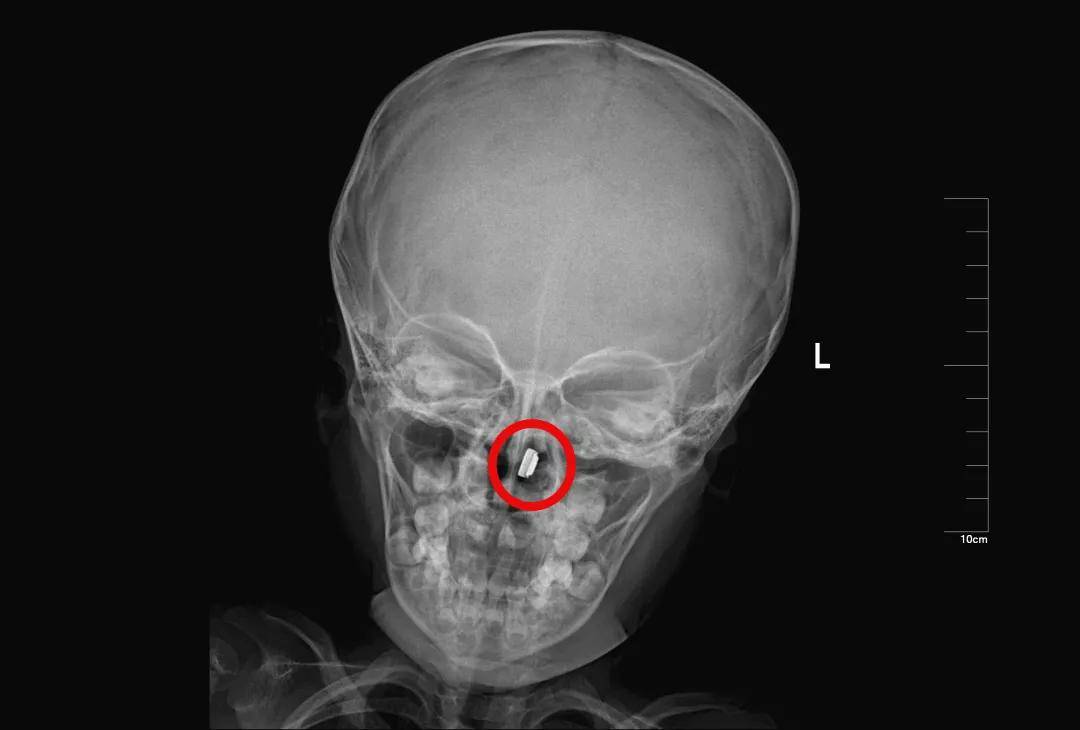

2岁·电池

纽扣电池塞入鼻腔一天。幸好电池停留在了鼻腔,没有进入肺部或胃里。

如果电池在胃中被胃酸腐蚀后会崩解,进而流出腐蚀性液体,腐蚀性的液体有可能造成孩子的终身残疾。